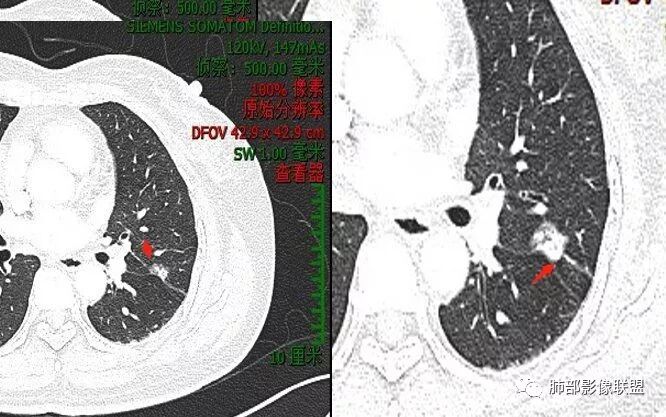

马宁强:考虑肉芽肿性病变,隐球菌可能彭君:左肺上叶舌段混合毛玻璃密度结节 边缘清 有分叶毛刺 斜裂胸膜凹陷征 考虑腺癌可能王秀仙:左肺上叶结节,部分边缘磨玻璃清晰,有分叶毛刺,支气管通过并扩张,其外侧小叶间隔不规则增厚,胸膜牵拉,考虑腺癌。鉴别慢性炎症。田园晚风:左肺上叶多个小结节融合呈分叶状,可见叶间裂牵拉,考虑腺癌张帅:左肺上叶后段结节,内可见支气管穿过,病灶周围有少许毛刺,病灶边缘有浅分叶,对叶间胸膜有牵拉,部分位置呈对叶间胸膜推移。考虑为恶性病变,腺癌?。杨泽锋:混合型磨玻璃结节,边缘有膨隆、有凹陷,明显的胸膜牵拉,考虑腺癌可能大;内部支气管通畅、似乎有鬼脸征,所以鉴别隐球菌Lotus:病灶内部有结节感,这个大小似乎是次级肺小叶的大小,考虑炎性,有冠位最好了。但是胸膜牵拉有些恶性提示心包右侧软组织密度影考虑心包隐窝Yiren Sishui(厶水伊人):叶间裂有膨隆有凹陷,考虑恶性,腺癌可能

徐婕:同意恶性腺癌可能岁月:女,56;空泡,分叶毛刺,牵拉线,胸膜凹陷征,有强化,浸润性腺癌。THINKER:左舌见结节,膨胀为主,部分收缩,分叶丶短丶硬毛刺,牵拉斜裂,有小空泡,支气管穿行,有强化,常规腺癌丽:左肺上叶近胸膜下结节,胸膜牵拉,边缘膨隆,并可见深分叶及毛刺,内有空泡,增强后可见强化,倾向腺癌淘时光:混合磨玻璃结节,实性部分较多,内见支气管穿行,腺癌首先考虑了…☀:左肺上叶结节影,实性,边缘分叶征,其内可见空泡,部分膨胀生长,局部叶间裂牵拉上移,叶间裂光滑增厚,首先考虑肿瘤黄棘:左肺上叶结节,边缘彭隆, 周围磨玻璃影边界清,内部可见扩张支气管,叶间胸膜牵拉,考虑腺癌心灵鸡汤:左肺上叶舌段近斜裂处混合性结节,以实性成分为主,有分叶、毛刺,牵拉邻近叶间、脏层胸膜,增强有强化,影像学上看偏恶性,分类LU-RADS 4C类,MIA浸润性腺癌可能,鉴别肉芽肿性病变、隐球菌,请老师指点!THINKER:这个如果是腺癌,应该是IAC了,过MIA了,个人看法,罗老师一切∮随缘:左肺叶裂胸膜下结节,边缘收缩弱,周围有GGO,边界清楚,形态欠规则,其内似有支气管穿行,增强扫描轻度均匀强化,考虑1肉芽肿性病变(隐球,炎性假瘤)2:浸润性腺癌Clover:考虑腺癌,实性为主混合有少许边界清晰ggo,边缘膨隆,其内支气管气象不规则,有收缩力。Coke with ice:还有一个疑问请教一下:这个是混合磨玻璃结节还是实性结节?个人倾向于后者。心灵鸡汤:有部分磨玻璃Coke with ice:实性结节周围GGO初学者:实性,周围有毛玻璃晨:有浅分叶,有毛刺,有叶间裂牵拉,内有囊泡,考虑腺癌。初学者:稍等,我等会开电脑看,但是感觉和你们一样,感觉是一个典型病例来着Coke with ice:这个人我也倾向于腺癌。但是诊断腺癌还有一个比较疑惑的地方,肺窗病变密度显示比较实,但是纵隔窗病灶范围明显比肺窗小,腺癌可以解释的通吗?张小兵:混合磨玻璃结节,内见支气管穿行,分叶,胸膜牵拉从凹陷处进入,腺癌首先考虑小微:

Coke with ice:这里是不是脐凹征呢?对诊断方向很重要。待老师们指点。

脐凹、分叶

Coke with ice:@南边 老师这里是不是脐凹征这个好像和胸膜相连,不是标准的脐凹征南边:定义上是指血管、支气管从凹陷处进入远端是出去进入、出去是两个概念

近肺门侧是进入,意味着血管支气管顶住,导致局部的肿瘤生长受限;出去是指血管穿过肿瘤从远端延伸出去所以我认为有价值,但不是脐凹征。